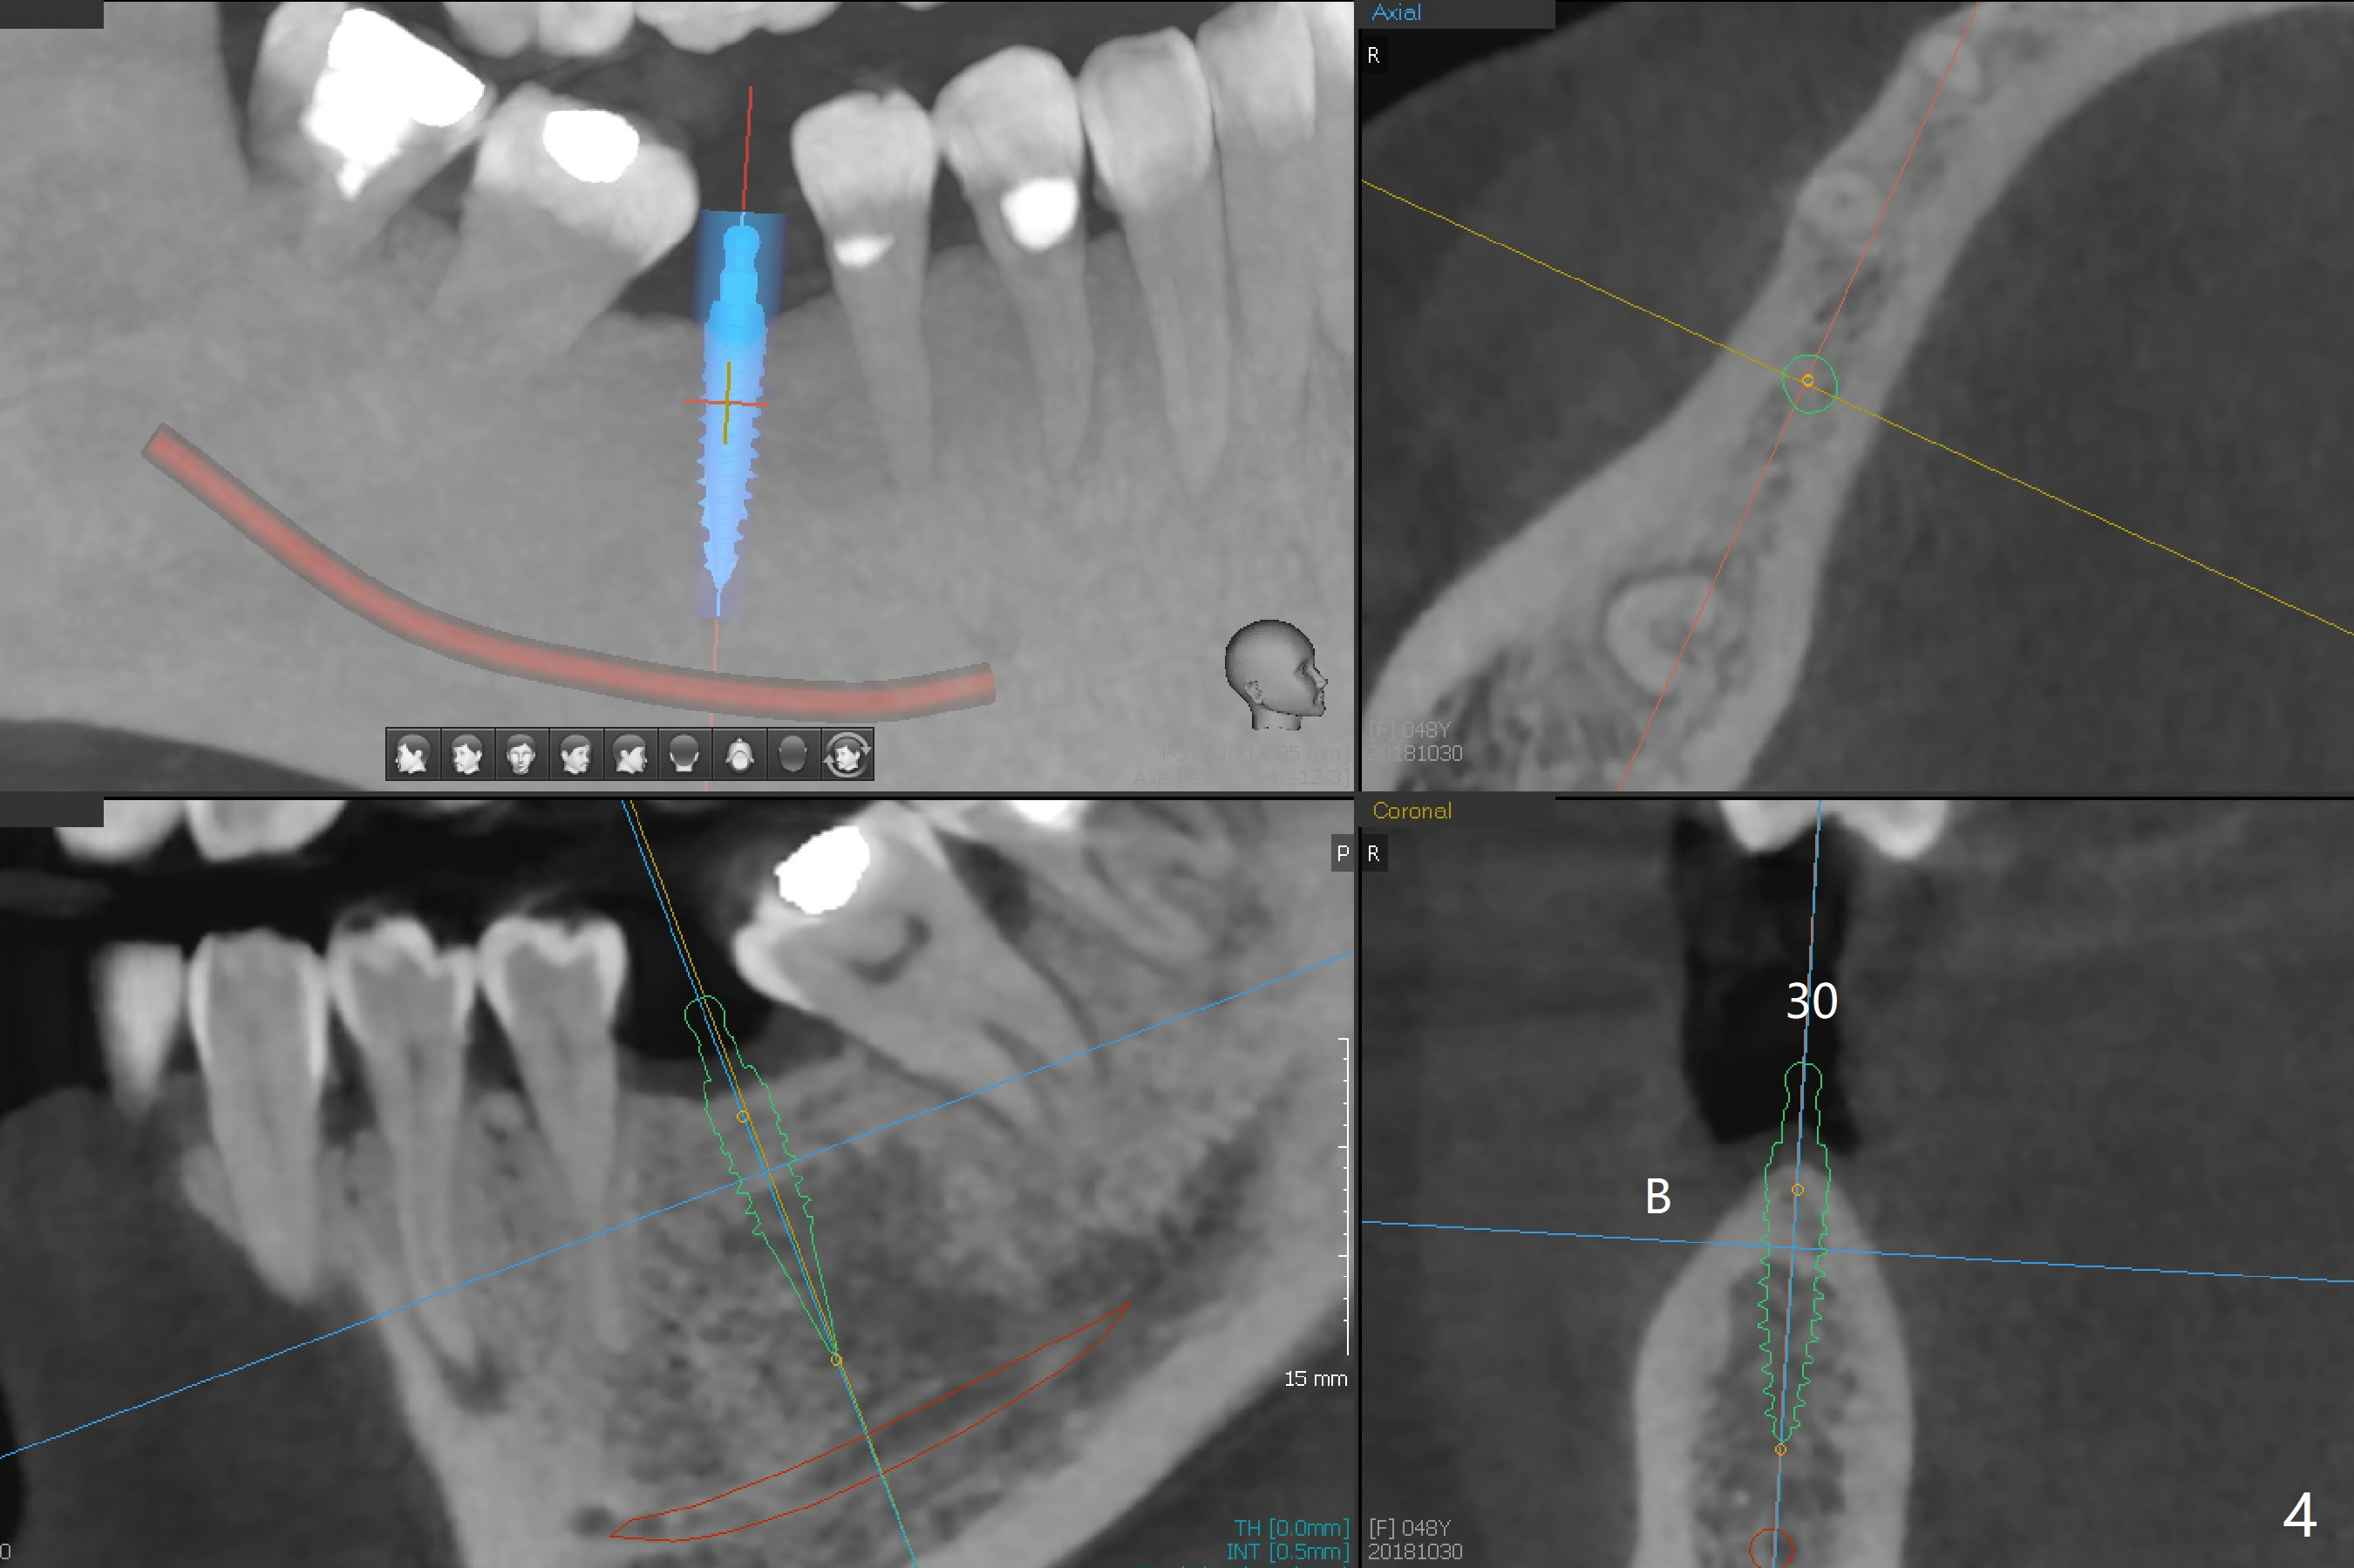

A 48-year-old woman, dentophobic, presents to clinic with request of redo #8,9 composite, which have dislodged twice in the last 6 months. Restoration failure is at least in part due to partial edentulism (#18,19,30, Fig.1). After discussion, she agrees to have implants at #18 and 19 first with guide (Fig.2,3). An ideal treatment plan for #30 (narrow mesiodistal space) would be extraction of #32 (ML fracture), uprighting of #30 and placement of a normal diameter implant. Considering dentophobia and living far from the office, a practical option will be a 3x12 mm 1-piece implant (Fig.4).